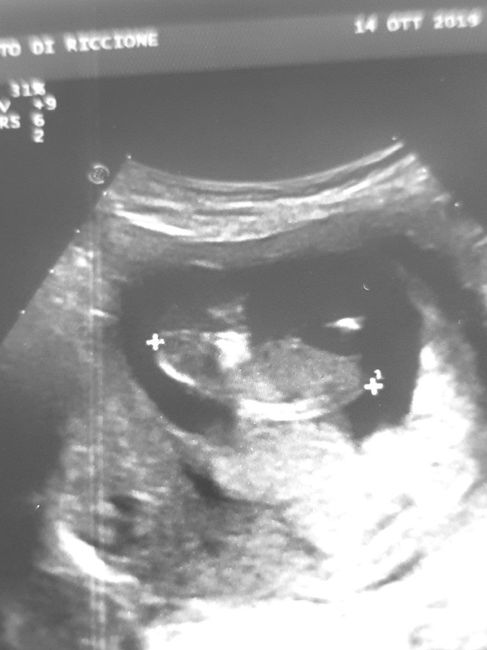

Mancano ancora tantissime settimane alla morfologica, che avrò il 15 Luglio, mi ritrovo spesso a fantasticare se sarà Filippo o Lucrezia, io mi sento maschio ma non si sa mai.

Mi affido a voi esperte di Nub Theory, cosa dite maschio o femmina??